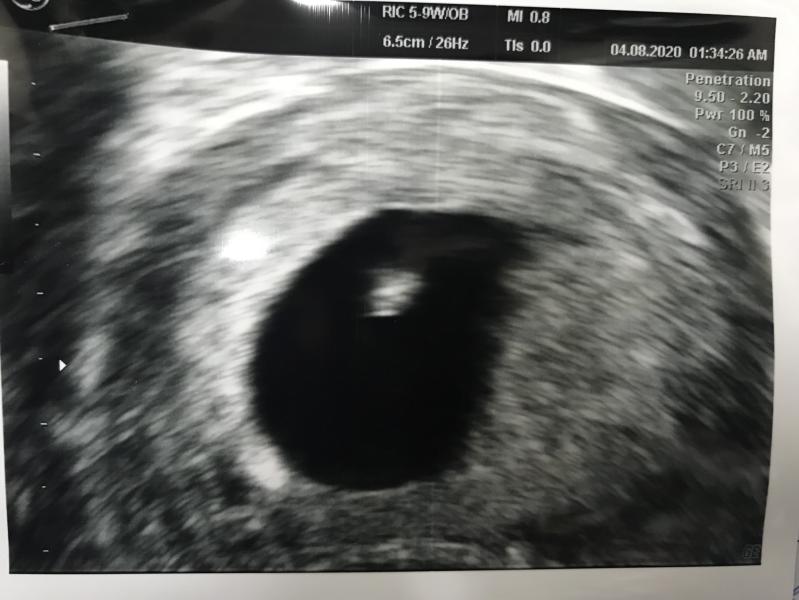

6 недель 6 дней

Сердце +

60